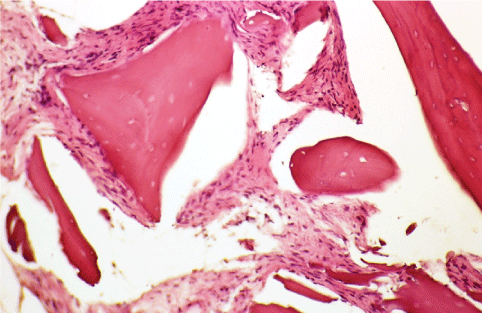

In the MB group, a mean RW, HVC, and HLC reduction of 1.25 ± 0.7 mm, 1.18 ± 0.8 mm, and 1.12 ± 0.9 mm respectively occurred. In the MP group, a mean RW, HVC, and HLC reduction of 1.19 ± 0.4 mm, 1.21 ± 0.8 mm, and 1.09 ± 0.6 mm, respectively was found (Table 1). No differences in dimensional vertical and horizontal changes were encountered at the extraction sockets treated with MB and MP. Histomorphometrically, in sites treated with MB the percentage of newly formed bone was 49.08 ± 3.7, and the percentage of connective tissue was 16.37 ± 4.9, while in sites treated with MP, newly formed bone represented 57.13 ± 2.8, and non-mineralized connective tissue 13.65 ± 3.6. In the MB group, the mean percentage of residual graft particles and osteoid tissue was 13.49 ± 2.8, and 21.06 ± 3.8, respectively, while in the MP group, the same percentages were 11.74 ± 4.7, and 17.63 ± 3.8 (Table 2). Histomorphometrically, differences between MB and MP groups were statistically significant (p < 0.05). In Figure 1, Figure 2, Figure 3 and Figure 4 is reported the histological analysis of two sites treated with BM and PM, respectively.

Figure 3: Histological micrographs of vertical sections of extraction socket, and treated with collagen membrane and porcine derived-bone (Ematossin eosin, 50X). View Figure 3

Figure 4: Histological micrographs of vertical sections of extraction socket, and treated with collagene membrane and bovine derived-bone (Ematossin eosin, 50X). View Figure 4